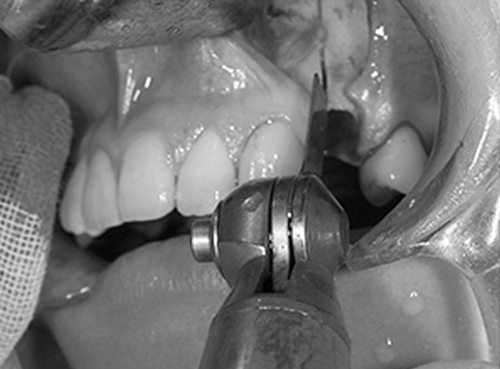

6. 骨を削ります

デザインで確認をした骨の切除範囲と骨の切離範囲に沿って骨切りをおこないます。骨切離は、骨がやけどをしない様に、生理食塩水を注水して、骨を冷やしながらエンジンやドリルで骨を切ります。

痛くありませんし、無意識の真っただ中ですから、振動も感じません。安心してください。この時に、歯の根元を傷つけないように、歯の根の先から5mm以上離します。

骨はコの字型に切ります。水平の骨切り線は、歯の根や神経を傷つけないよう、下の犬歯の根の尖端から5mm以上下方におこなっています。

下あご犬歯の根の尖端は、剥離した部分から見える骨から透けて見えることが多いので、傷つけることはありません。抜歯した歯の根の長さを参考にすることもあります。

抜歯した歯の部分の骨を削って、後ろに下げるために必要な骨のすき間を作ります。この部分の骨を削りすぎると、手術後に骨のすき間ができてしまいます。その他、骨と骨、歯と歯のすき間ができてしまう時もあります。下顎犬歯、下顎小臼歯が傾いてしまったり、部分的な歯周病になり、骨が融けてしまったり、歯が抜けてしまうこともあります。この部分の骨の削除はこの手術では、最も大切な手術のパートヤマ場と言えます。

カンファークリニックでは、模型を使用したモデルサージェリー、シミュレーション手術をおこなって、細心の準備と注意をしながら手術をおこなっています。骨を削る機械は専用のサジタルブレード(刃先)を使います。 水平的な骨切りと、垂直的な骨切りを組み合わせて、骨が後ろに下がるように骨を削り、骨を動かします。